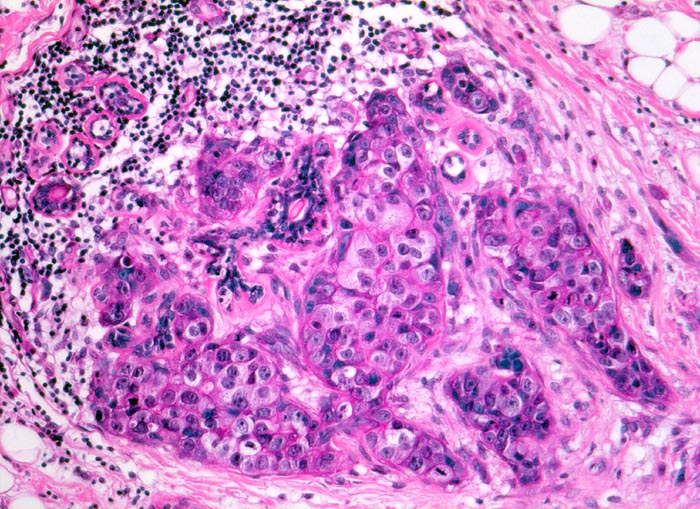

invasives duktales Mammakarzinom: Kanzerisierung eines Läppchens

Das Karzinom hat sich retrograd über den Ductus lactiferus in die Azini eines Läppchens ausgebreitet. Die läppchenförmige Anordnung der tumorbefallenen Azini ist noch erkennbar. Ein einzelner Azinus ist nicht tumorbefallen. Das Karzinom wächst an dieser Stelle nicht invasiv. Die tumorinfiltrierten Tubuli sind von einer Basalmembran umgeben.

Makroskopisch: derber weisser Herd von 2.2cm Durchmesser im oberen äusseren Quadranten.

Die Patientin hatte bei der Selbstuntersuchung einen harten Knoten in der rechten Mamma palpiert. Nach dem Nachweis von Karzinomzellen in der Feinnadelpunktion wurde eine Lumpektomie durchgeführt. Die intraoperative Schnellschnittuntersuchung ergab tumorfreie Resektionsränder.